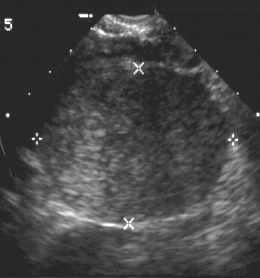

Imaging features of simple cysts

Hemorrhagic ovarian cysts